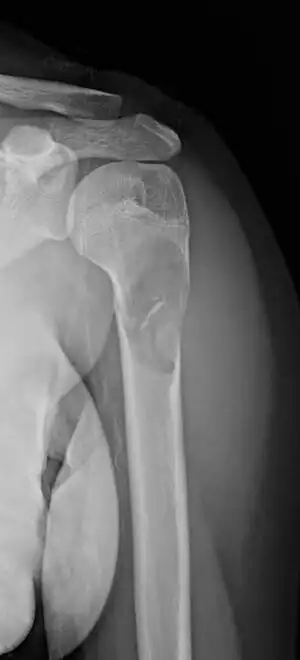

Unprovoked break in the long bone of the upper arm,, with "fallen leaf" sign. -